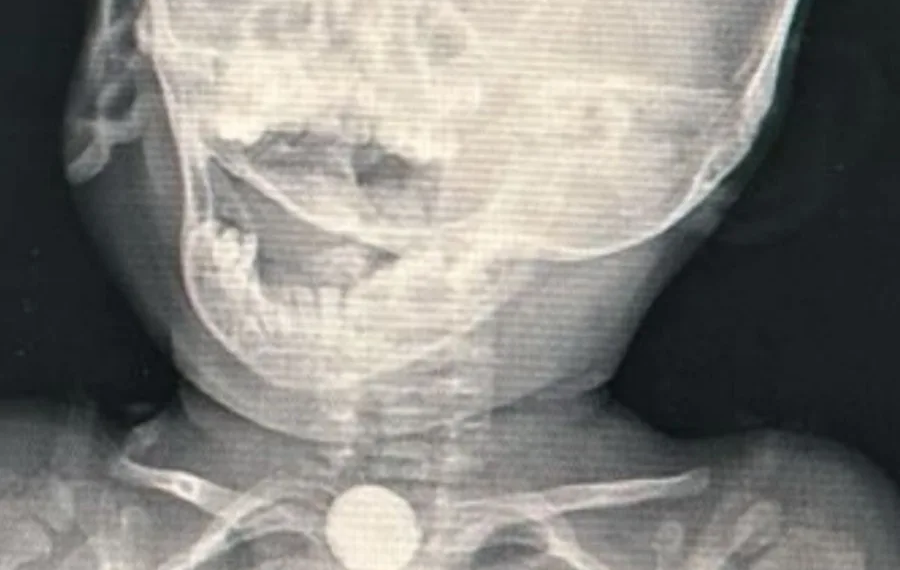

“A mãe não queria vir, por não falar direito português, mas a convenceram e ela veio. Foi realizada uma radiografia e foi identificada que era uma bateria, que é algo muito perigoso”, informou o médico.

“Porque a bateria rompe e começa a soltar íons, alcalinos que fazem uma lesão muito grande da mucosa do esôfago. Nós retiramos no domingo pela manhã”, disse ele, afirmando que o processo foi difícil, já que o objeto era muito grande para a criança. “Tinham várias lesões graves na mucosa do esôfago, mas ainda não tinha perfuração”, explicou.